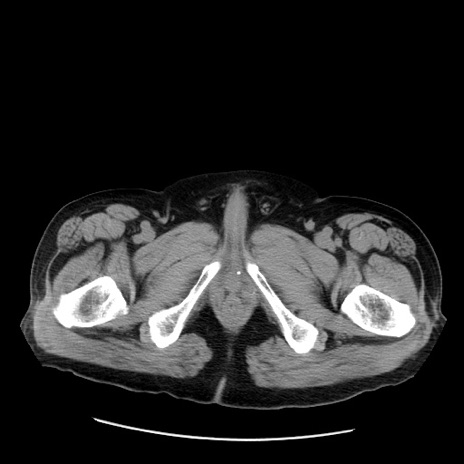

症例20(横断像)

【症例】 60歳代男性

【主訴】 腹部膨満、嘔吐

【現病歴】5日前頃より倦怠感を認め食事量減少し4日前の朝嘔吐、食事摂取困難となった。 3日前近医受診し点滴施行され整腸剤などを処方された。 当日他院を受診し、腹部膨満著明、炎症反応の上昇(CRP10.8、WBC11200)あり、紹介受診となる。

【身体所見】 意識JCS1 受け答えがはっきりしないBP 111/57mHg、 P 67bpm、、BT35.2°C、SpO2 97%(RA)、 腹部:膨隆、打診で鼓音あり、全体的に圧痛有り、腸蠕動音(-)、反跳痛ははっきりせず。

【データ】WBC 11400、CRP 14.20